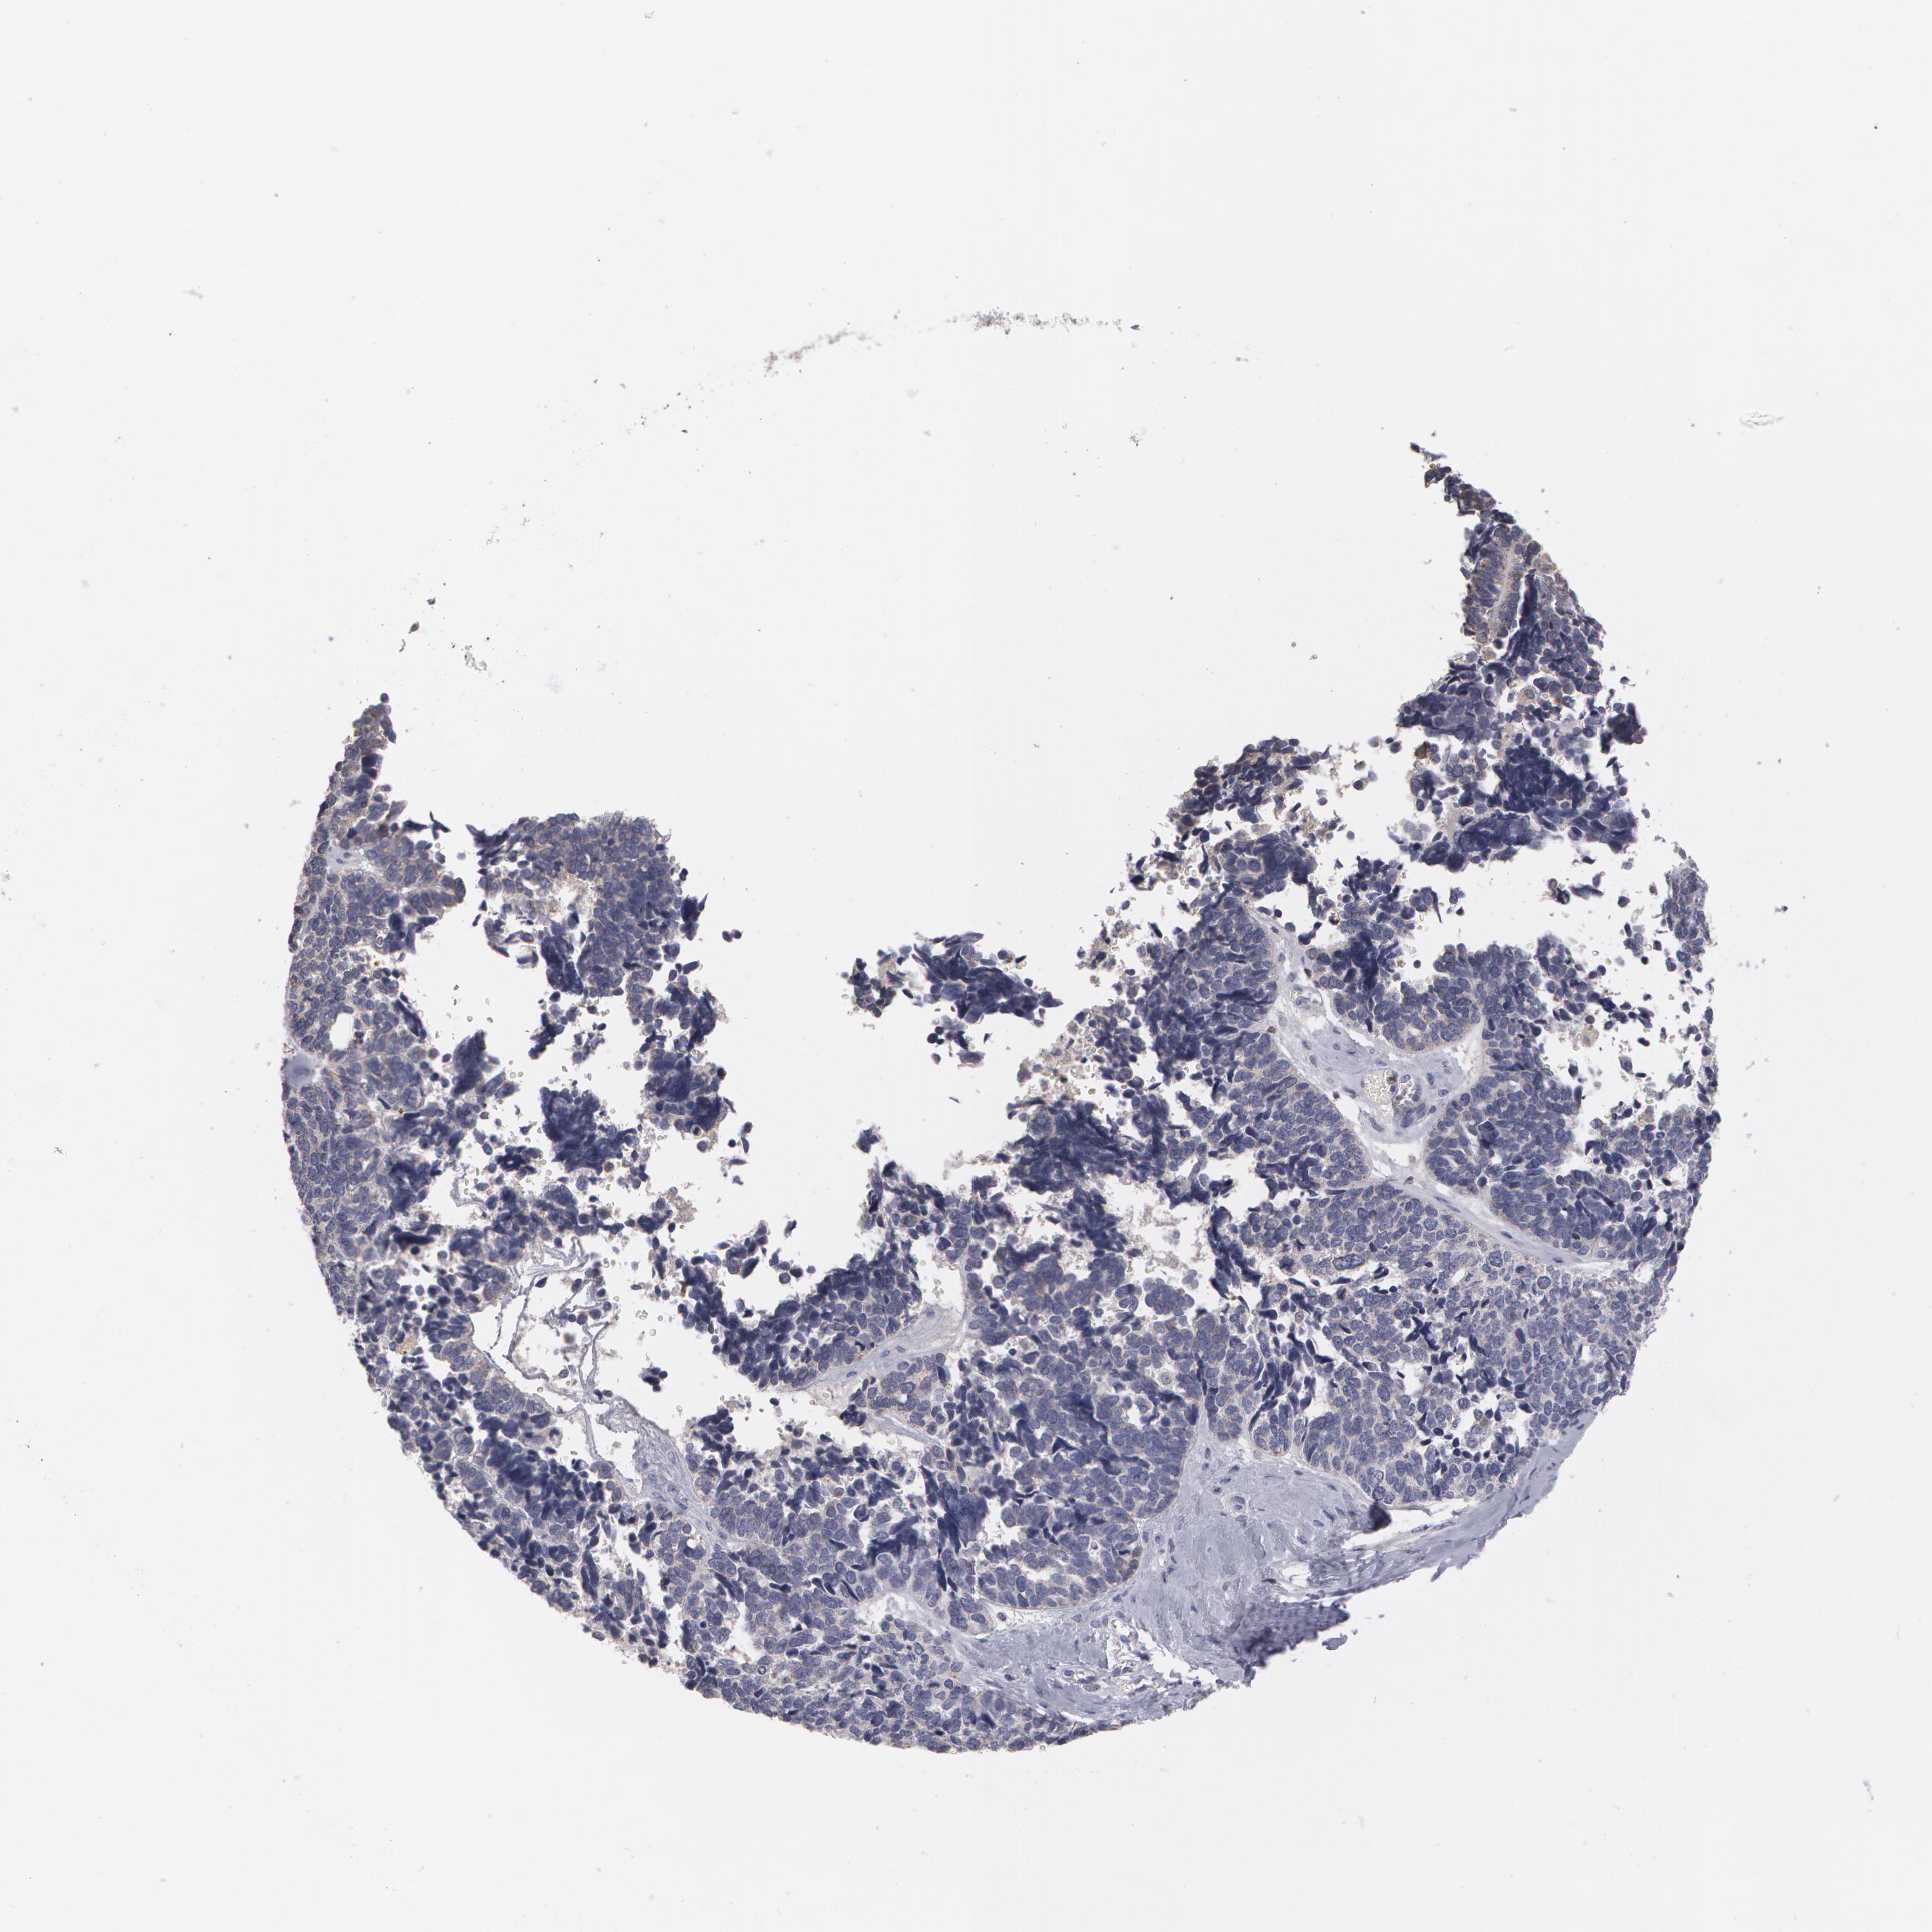

OVARIAN CANCER - Protein expressioni

A mouse-over function shows sample information and annotation data. Click on an image to view it in a full screen mode. Samples can be filtered based on level of antibody staining by selecting one or several of the following categories: high, medium, low and not detected. The assay and annotation is described here.

Note that samples used for immunohistochemistry by the Human Protein Atlas do not correspond to samples in the TCGA dataset.

Antibody stainingi

Antibody staining in the annotated cell types in the current human tissue is reported as not detected, low, medium, or high, based on conventional immunohistochemistry profiling in selected tissues. This score is based on the combination of the staining intensity and fraction of stained cells.

Each image is clickable and will lead to virtual microscopy that enables deeper exploration of all samples and also displays staining intensity scores, fraction scores and subcellular localization as well as patient and tissue information for each sample.

Antibody HPA055838

Cystadenocarcinoma, mucinous, NOS